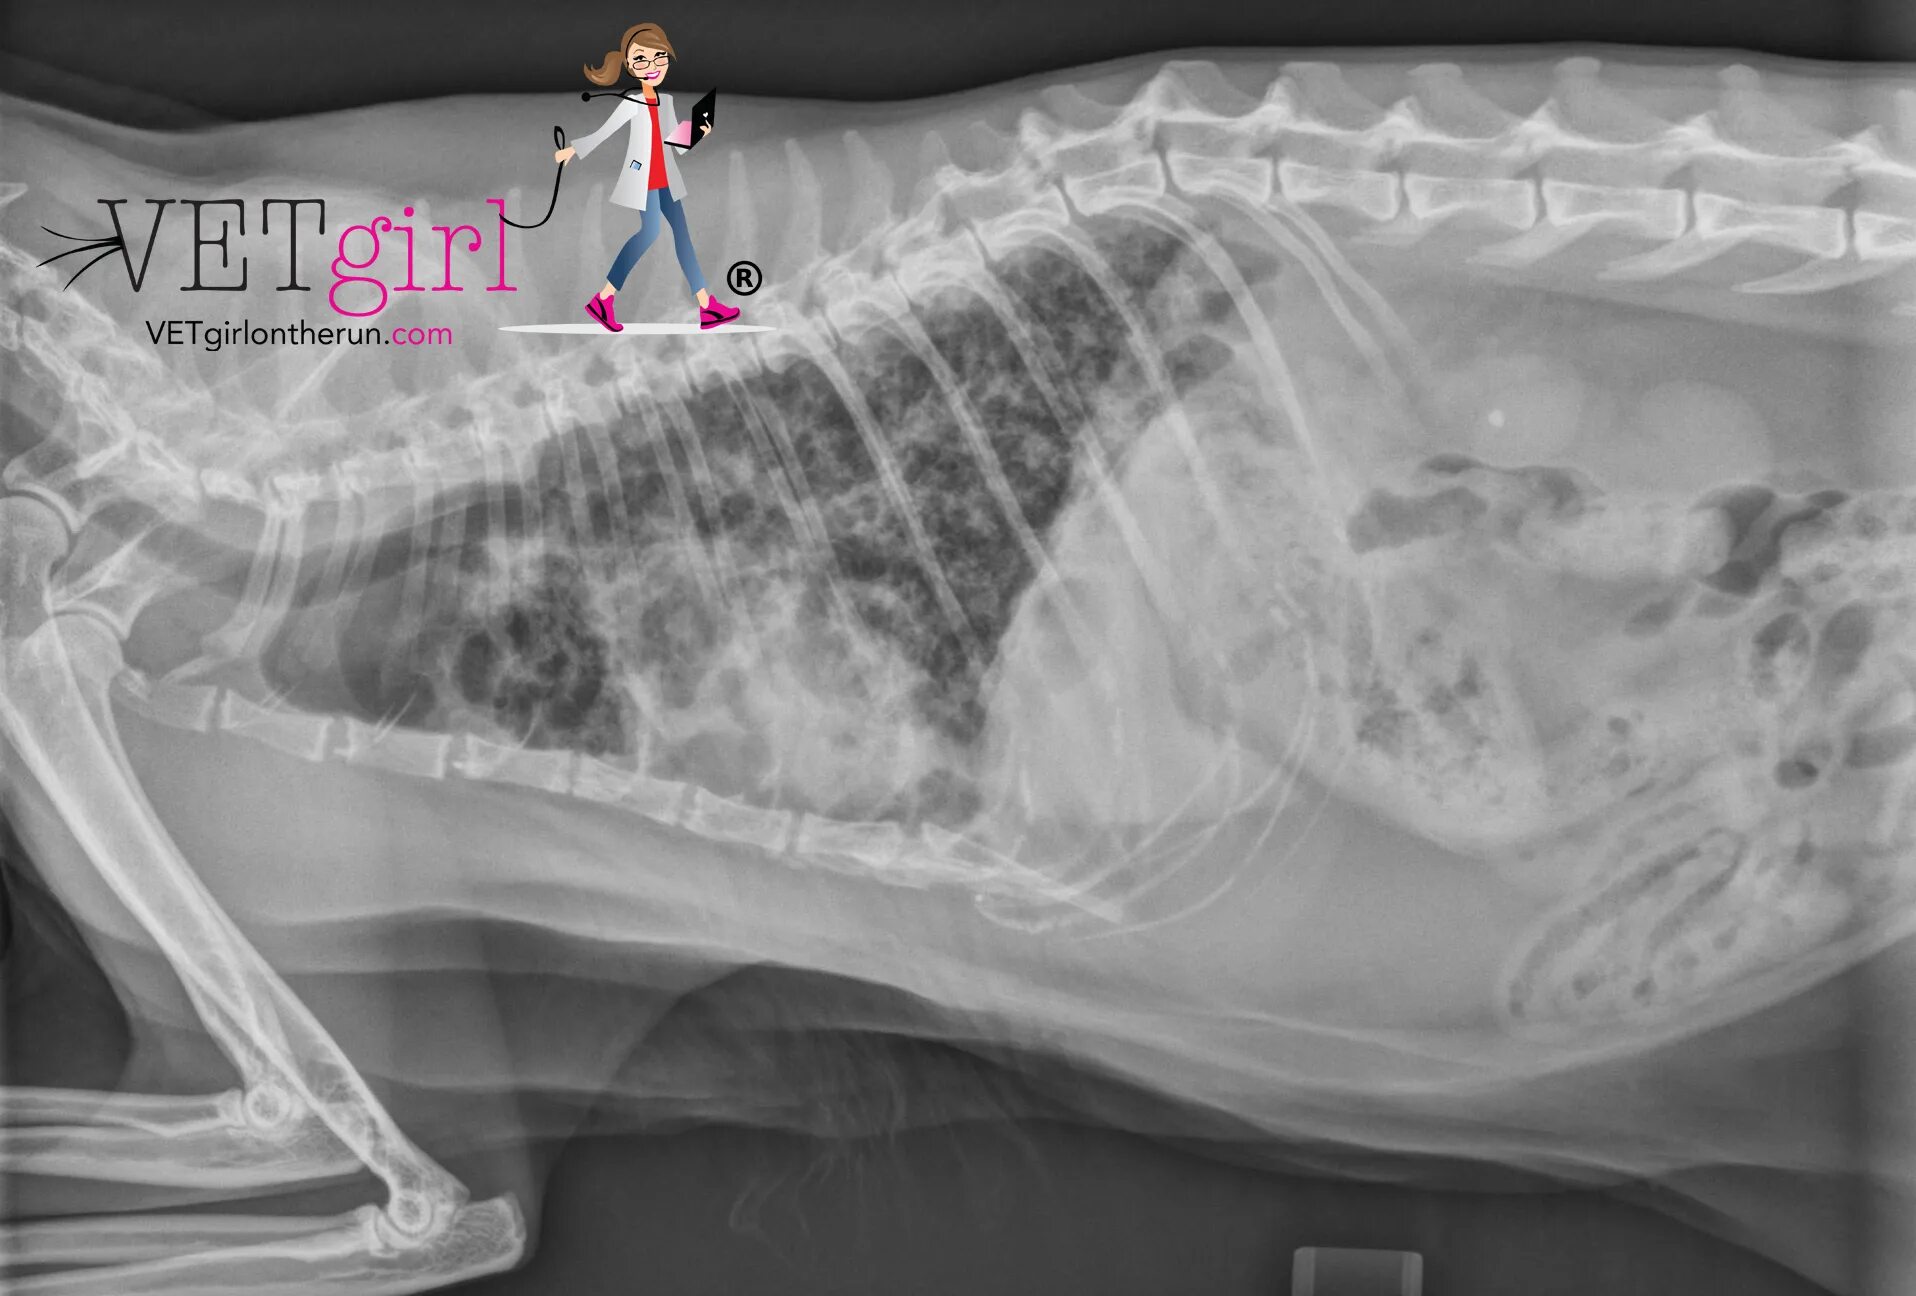

Астма у кота